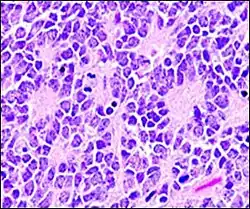

Flexner–Wintersteiner rosettes in Retinoblastoma.

Flexner–Wintersteiner rosettes, a spoke-and-wheel shaped cell formation seen in retinoblastoma and certain other ophthalmic tumors,[3]) have been described as a form of palisading.[4]

Unlike the center of the Homer-Wright rosette, the central lumen is devoid of fiber-rich neuropil. The defining feature of this rosette is the central extension of cytoplasmic projections of the surrounding cells. Like the Homer Wright rosette, the Flexner–Wintersteiner rosette represents a specific form of tumor differentiation.[5][6][7][8] Electron microscopy reveals that the tumor cells forming the Flexner–Wintersteiner rosette have ultrastructural features of primitive photoreceptor cells.[9] Furthermore, the rosette lumen shows similar staining patterns as in rods and cones,[10] suggesting that Flexner–Wintersteiner rosettes represent a specific form of retinal differentiation. In addition to being a characteristic finding in retinoblastomas, Flexner–Wintersteiner rosettes may also be found in pinealoblastomas and medulloepitheliomas.[5]